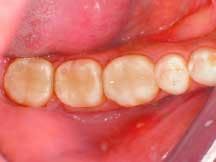

For the Class II restoration on Tooth No. 19, a thin layer of flowable composite (4 Seasons Flow) was applied in the gingival box area, as well as any other deep preparation areas, and cured for 20 seconds using a curing light at ≥500mW/cm2. For the restoration build-up on Teeth Nos. 17 through 19, each cusp area was developed using .5 mm to 1 mm increments of the A 3.5 dentin shaded composite, building each increment out in a cup-like manner (i.e., as described by Lee Culp, CDT), rather than lobing the cusps. Each increment was then "tack cured" through the tooth for five seconds per increment through whichever cusp had been built up (Figure 3).

3